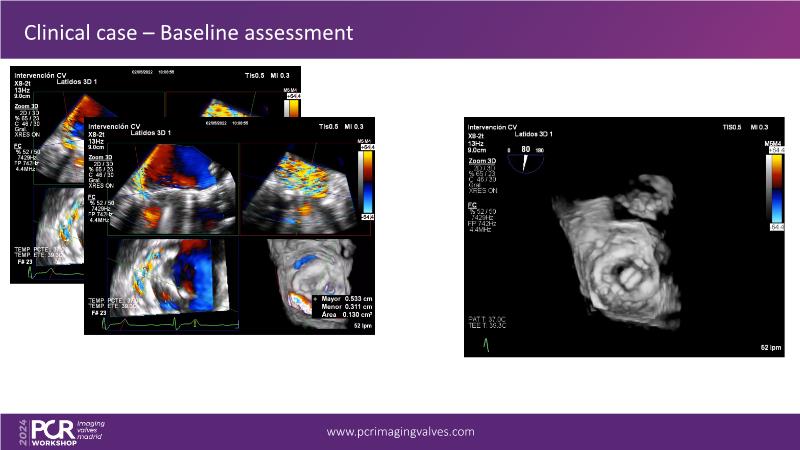

Explore cutting-edge transcatheter valve interventions for mitral and aortic valve disorders, including valve-in-valve procedures and management strategies for paravalvular leakages, and learn about diagnosing and treating mitral annular calcification and transcatheter options in infective endocarditis.

- To get tips and tricks for guidance of transcatheter intervention